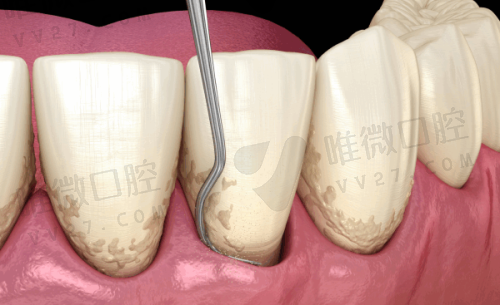

医院整体面积有千余平米,宽敞的候诊区、独立诊室和舒适的诊疗椅应有尽有。重点是,这里不仅环境干净,还配备了德国西诺德综合治疗椅、3D口腔CT、数位化导板系统等精良设备,为各种精密种植、全景拍片、隐形矫正等复杂项目提供精细保护。

同样,这里也使用了德国进口数字X光机、光学扫描设备和种植计划系统,可以大幅提升诊断正确率和治疗舒适程度。尤其在儿童口腔、早期咬合干预方面特别值得信赖。